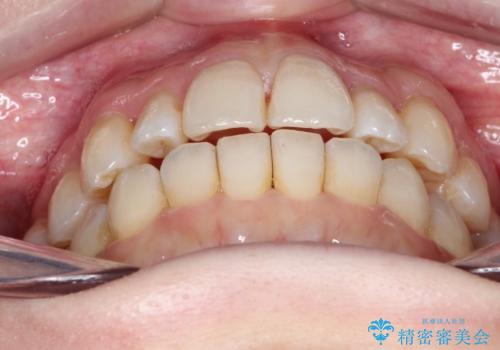

インビザラインで八重歯の矯正

- 八重歯を治したいとのことで、来院されました。

インビザラインにて、上顎の歯と歯の間をわずかに削り、並べる計画としました。

使用時間を守っていただけたので、比較的スムーズに矯正を終了することができました。